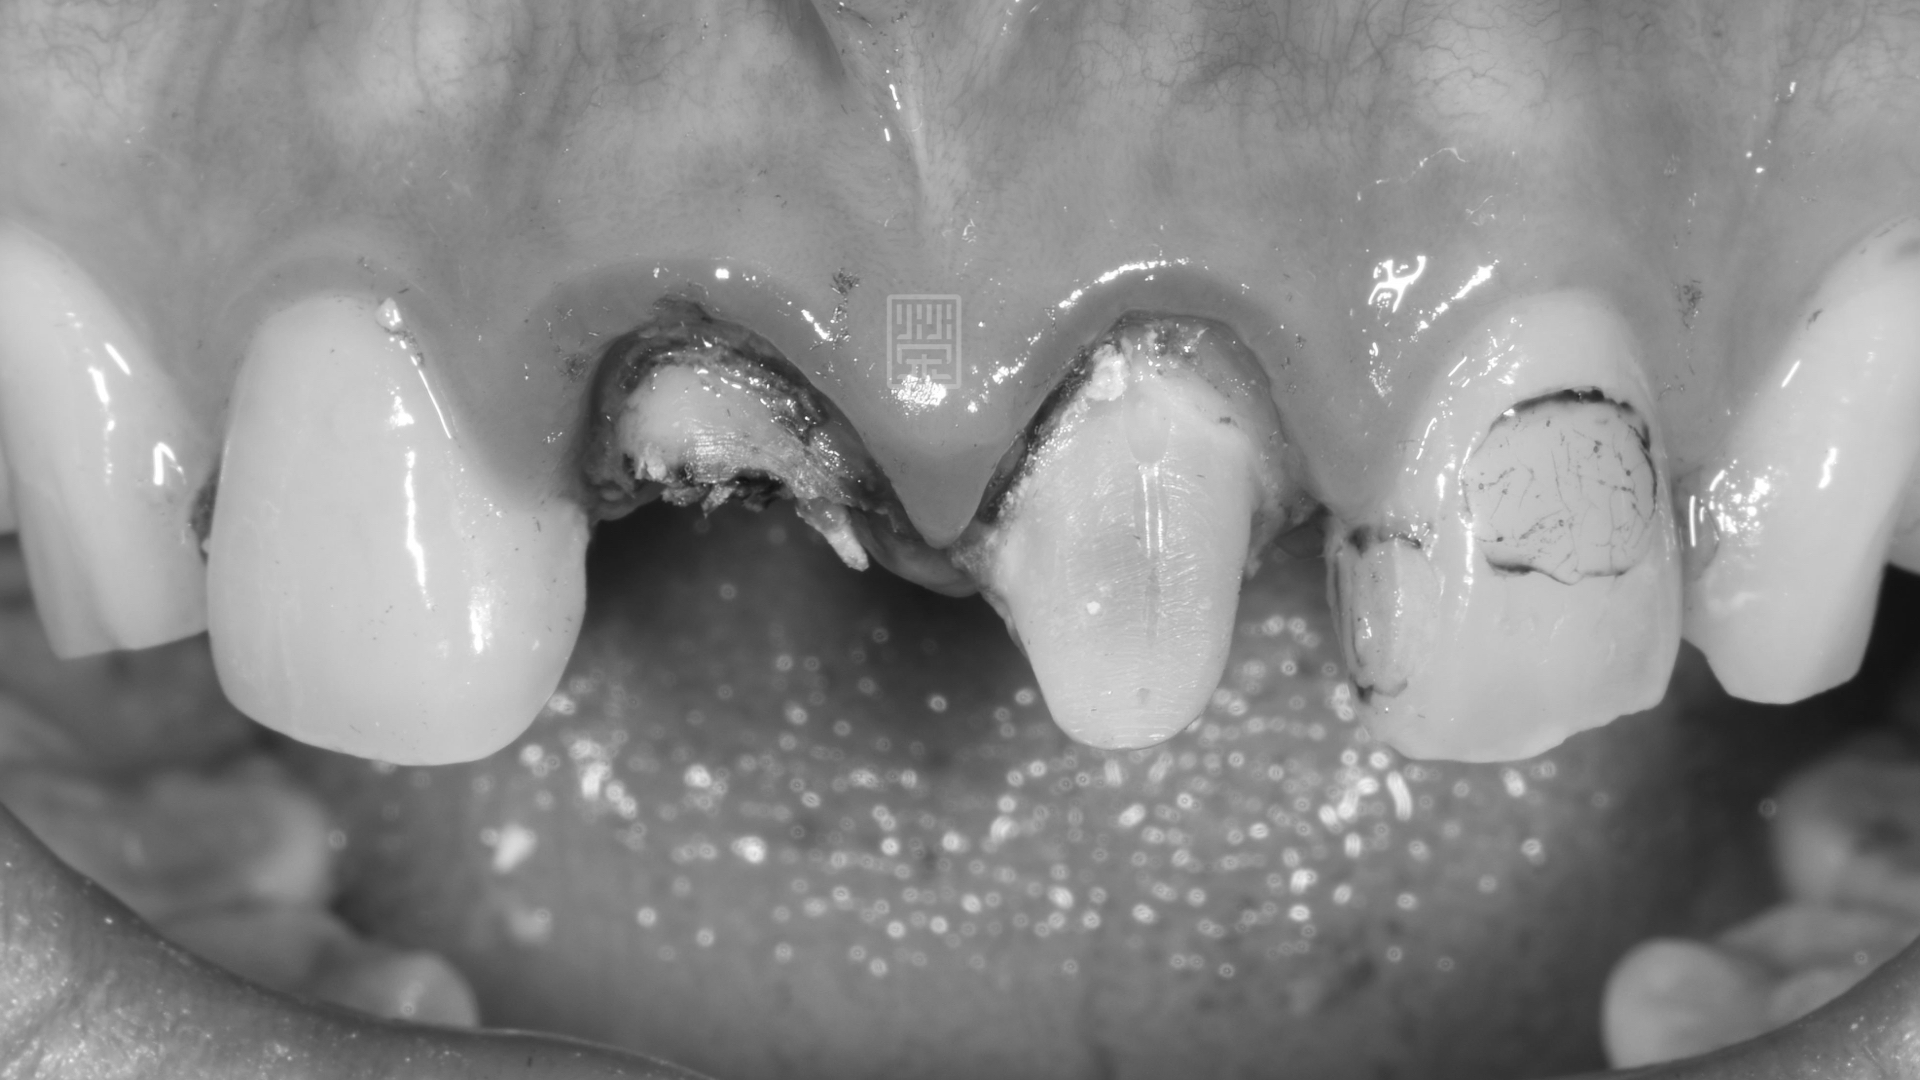

門牙舊假牙有異味